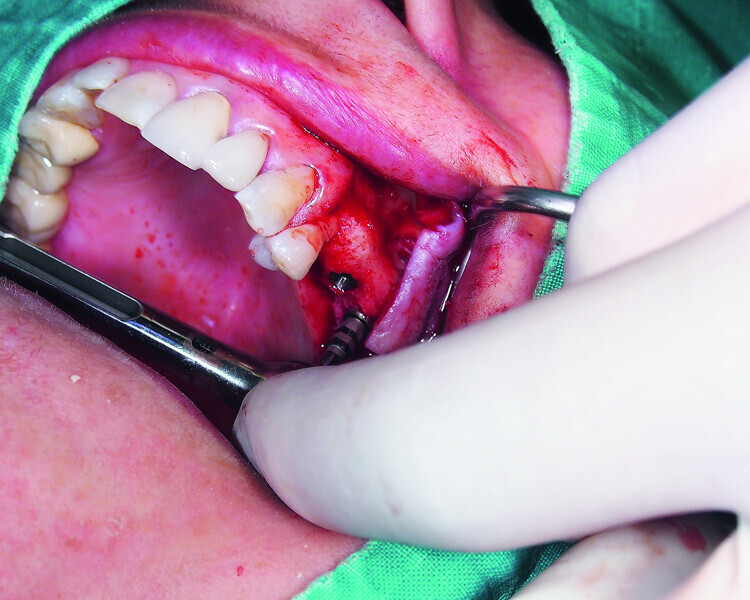

Fig. 15: Combination of full- and partial-thickness flap elevation.

Fig. 16: Mandibular ridge splitting with vertical cuts.